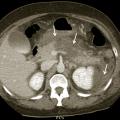

L’échographie abdominale a l’inconvénient d’être opérateur-­dépendante. Ses principales indications sont la lithiase biliaire et ses complications, des douleurs abdominales chez les patients minces et surtout chez la femme pour rechercher une pathologie gynécologique en utilisant le cas échéant des sondes endocavitaires. Ainsi, l’échographie est utile pour affirmer la lithiase biliaire et la cholécystite aiguë (fig. 1) ou objectiver une dilatation de la voie biliaire principale (VBP), rechercher une urétéro-hydronéphrose et des signes indirects en cas de colique néphrétique (fig. 2 et 3), débrouiller le diagnostic des douleurs abdomino-­pelviennes chez la femme.

L’échographie est essentielle, montrant un épaississement de la paroi vésiculaire à plus de 6 mm et la présence de calcul(s) ou « sludge » (fig. 1), sans dilatation de la voie biliaire principale (VBP). La complication principale est la péritonite et le choc septique souvent sur une gangrène de la paroi vésiculaire qui peut conduire de manière exceptionnelle vers le cholépéritoine.